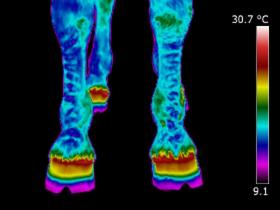

| DISTAL LIMB

| Thermography can point to potential conditions through changes in heat patterns, before the horse shows any clinical signs of injury. It can also reveal hidden signs that other diagnostic tools cannot. It gives us information we didn't know, we didn't know.

| | |  | | | I am very interested in the distal limb and thermography can be used to provide

you and your professional team additional information about conditions such as navicular syndrome,

laminitis, abscesses and corns. Importantly, it can give us information regarding hoof balance and weight-bearing. Hoof balance, often over looked, is a significant influence in the cause of lameness problems not only locally in the foot but throughout the musculature of the body through compensatory issues.